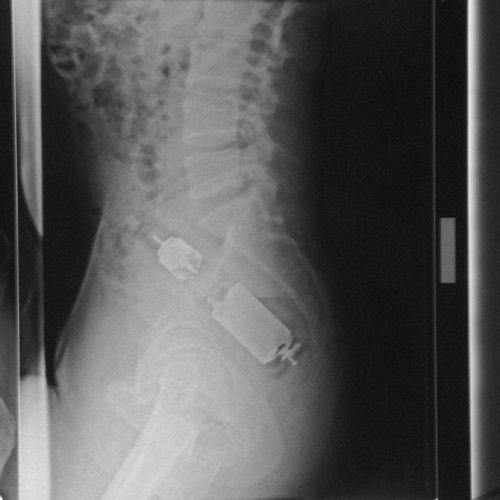

Под рентгеном